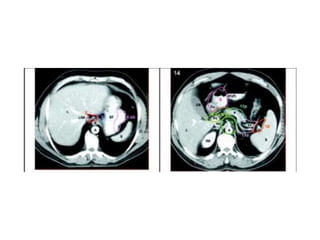

• A triphasic CT with oral and

intravenous contrast of the abdomen,

chest, and pelvis is imperative.

• In a study of 790 patients who

underwent MDCT prior to surgery, the

overall accuracy in determining T

stage was 74% and for N staging it

was 75%.

• MPR-MDCT(multi-planar

reconstruction-multidetector CT) with

combined water and air distention is

superior to conventional axial

imaging.

COMPUTED TOMOGRAPHY • A triphasicCT with oral and intravenous contrast of the abdomen, chest, and pelvis is imperative. • In a study of 790 patients who underwent MDCT prior to surgery, the overall accuracy in determining T stage was 74% and for N staging it was 75%. • MPR-MDCT(multi-planar reconstruction-multidetector CT) with combined water and air distention is superior to conventional axial imaging.